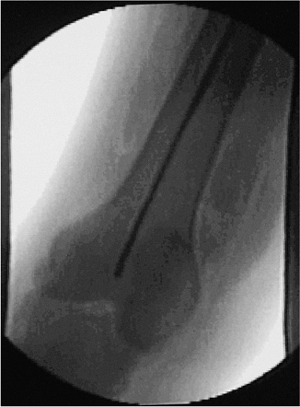

![]() |

Figure 20.10. Guide wire inserted to knee for reaming and length determination of nail.